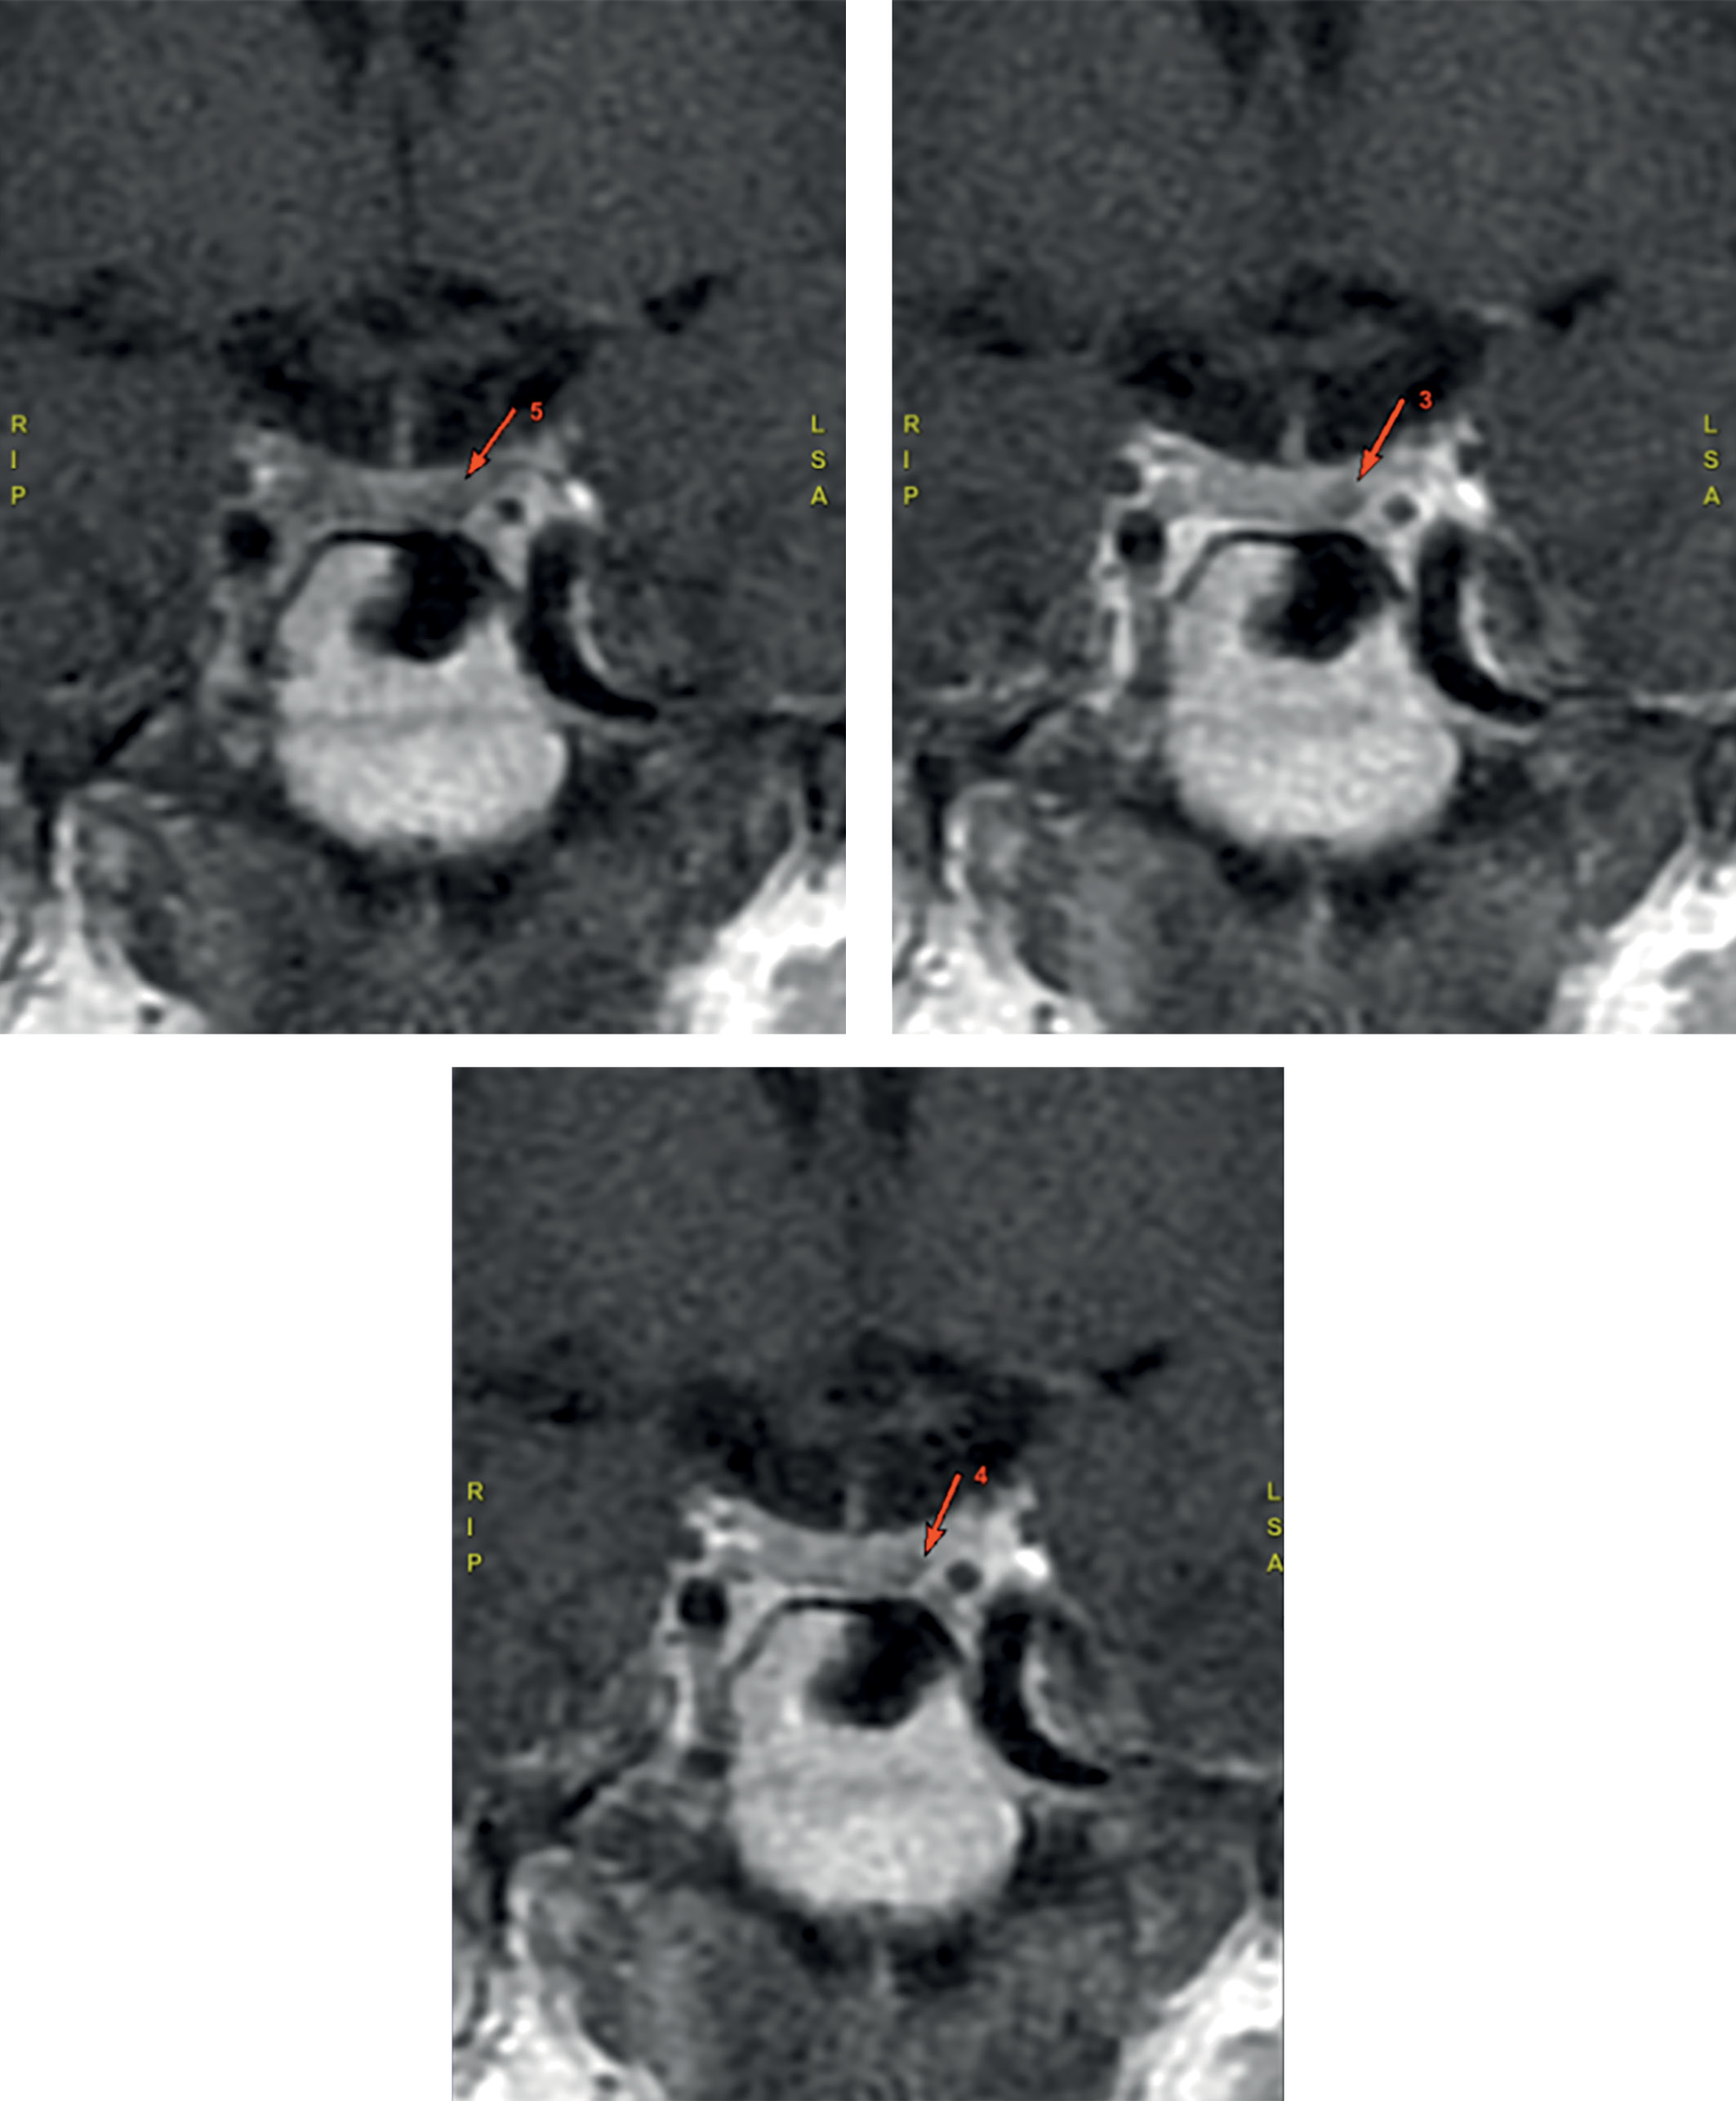

Проведен поиск источника эктопии. МСКТ легких и средостения не обнаружило патологических образований. В свою очередь, МСКТ брюшной полости и забрюшинного пространства подтвердила образование левого надпочечника овальной формы (рис. 2) размерами 37х30х46 мм, злокачественного фенотипа (плотностью 42/49/69/60 Hounsfield units (HU) в нативную/артериальную/венозную/отсроченную (15 мин) фазы контрастирования соответственно, абсолютный индекс вымывания (APW) — 33%, относительный индекс вымывания (RPW) — 13%; нерезкая диффузная гиперплазия обоих надпочечников. Образование левого надпочечника расценено как очаг эктопической секреции АКТГ.

Рисунок 2. Визуализация левого надпочечника на МСКТ органов забрюшинного пространства:

1 — красная стрелка указывает на левый надпочечник,

синяя стрелка — на опухолевое образование;

2 — красная стрелка указывает на левый надпочечник.